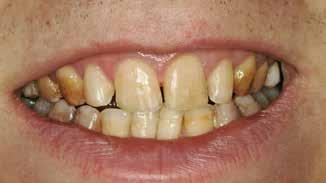

Beskrivelse af patienten Patienten blev henvist til specialistuddannelsen i pædodonti ved Universitetet i Oslo, da hun var syv år gammel, for diagnostik og behandling af tandudviklingsforstyrrelse i primære og permanente tandsæt. Pigen havde pollenallergi, var ellers sund og rask og havde intet medicinforbrug.

Klinisk undersøgelse viste emaljehypoplasier og hypomineralisering på 1+, +1, 2-, 1-, -1 og -2 (Fig.1). Hun havde Angle klasse II, pladsmangel i begge kæber og agenesi af -5. Der var isninger ved spisning og tandbørstning. Fundene var forenelige